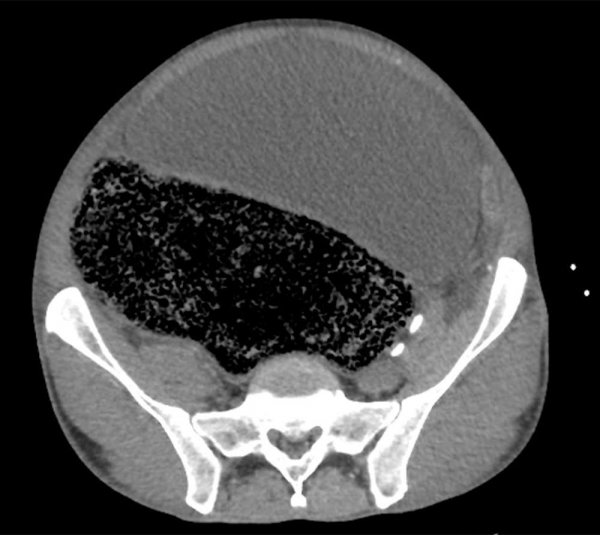

Специалисты обнаружили у мужчины синдром интраабдоминальной гипертензии — это значит, что давление в его животе было слишком высоким. Также у него были признаки почечной недостаточности и метаболического ацидоза — накопления кислот в организме.

Медики установили, что причиной этого состояния стало «массивное фекальное уплотнение неизвестной этиологии». Из-за него давление в брюшной полости поднялось, а также произошла окклюзия правой общей подвздошной артерии — ее проходимость нарушилась.

Мужчину прооперировали, чтобы удалить из кишечника лишнее вещество и снизить давление в брюшной полости. «Значительная фекальная дизимпакция была проведена вручную под общей анестезией, было удалено около двух литров кала», говорится в отчете медиков.